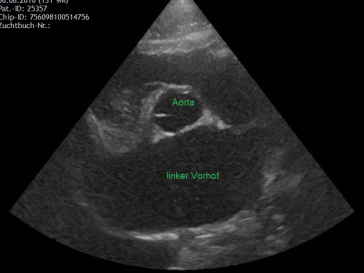

Mit dem Ultraschall werden der Herzmuskel und seine Anhänge dargestellt. Die verdickten Klappenteile, das Ausmass des Pendelblutes, der vergrösserte Vorhof und Ventrikel sowie die Druckdifferenzen sind mess- und darstellbar. Nach dieser systematischen Erfassung und Beschreibung beurteilt die Tierärztin den Schweregrad der Erkrankung und definiert Therapie-Optionen.

durch Rückfluss hochgradig vergrösserter Vorhof: Aorta/linkem Vorhof > 1.5

verdickte Ventrikelwand mit vergrössertem linkem Vorhof